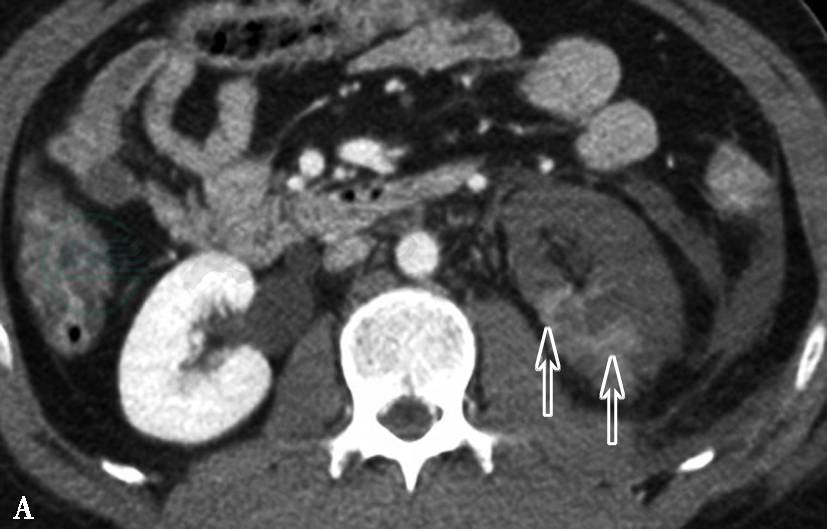

图3左肾动脉栓塞并肾梗死

A、B.增强扫描,左肾动脉主干显示良好,远端动脉腔内可见充盈缺损,同侧肾实质强化程度明显减低,局部可见小片状轻度强化区

引自:泌尿系统多层螺旋CT诊断学.第1版.ISBN:978-7-117-24109-0.主编: